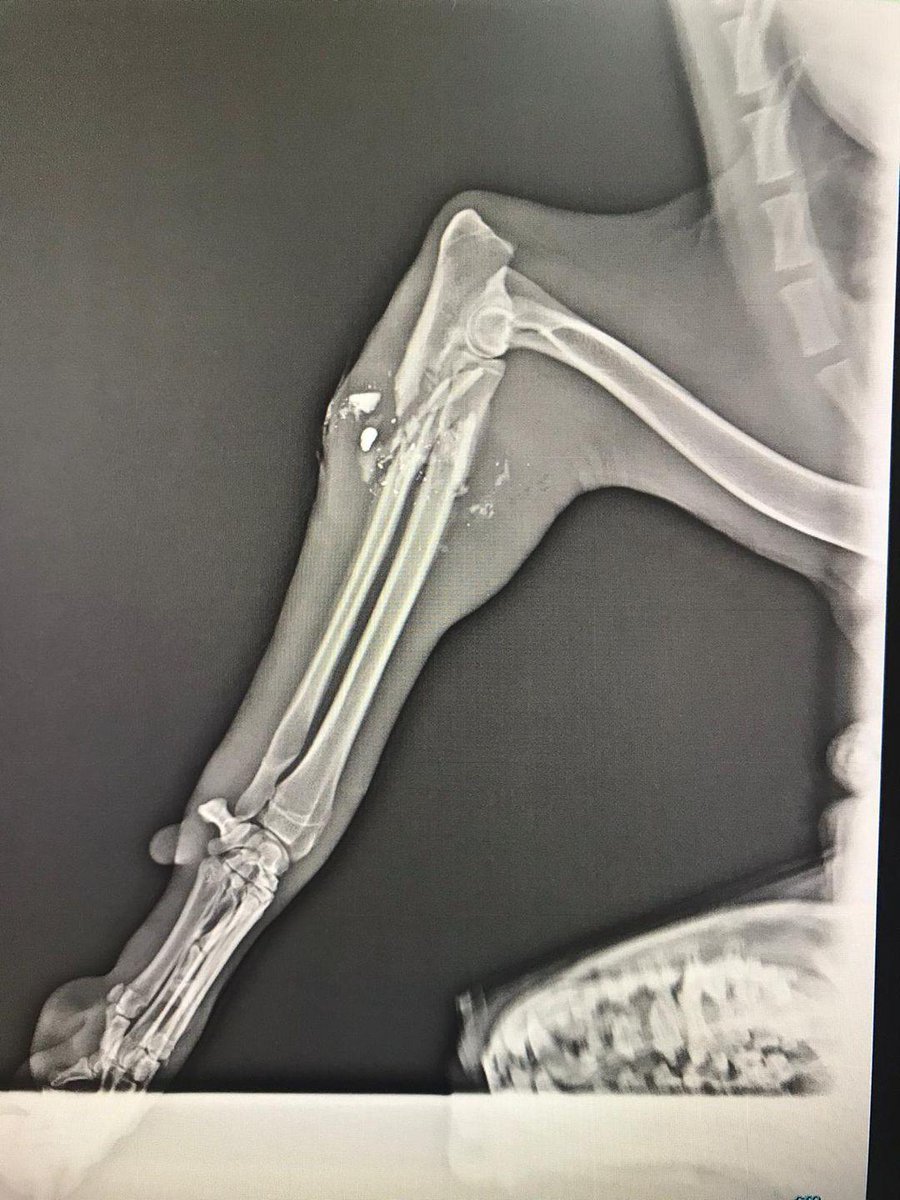

U GECE YATAĞINDA RAHAT UYUMA SEFERİHİSAR! PARAMPARÇA KEMİĞİ VE SALLANAN KOLUYLA DAĞLARDA AÇ GEZEN BİR KÖPEĞİN MİNİCİK VÜCUDUNDAKİ SANCISI SENİN KABUSUN OLSUN! ÇÜNKÜ SENİN PİSLİK KENTİNDE KÖPEKLERE SİLAHLA ATEŞ EDEN, KEMİKLERİNİ PARAMPARÇA EDEN CANİLER, KATİL ADAYLARI VAR!

PARAMPARÇA KEMİĞİ VE SALLANAN KOLUYLA DAĞLARDA AÇ GEZEN BİR KÖPEĞİN MİNİCİK VÜCUDUNDAKİ SANCISI SENİN KABUSUN OLSUN!

ÇÜNKÜ SENİN PİSLİK KENTİNDE  KÖPEKLERE SİLAHLA ATEŞ EDEN, KEMİKLERİNİ PARAMPARÇA EDEN CANİLER, KATİL ADAYLARI VAR!